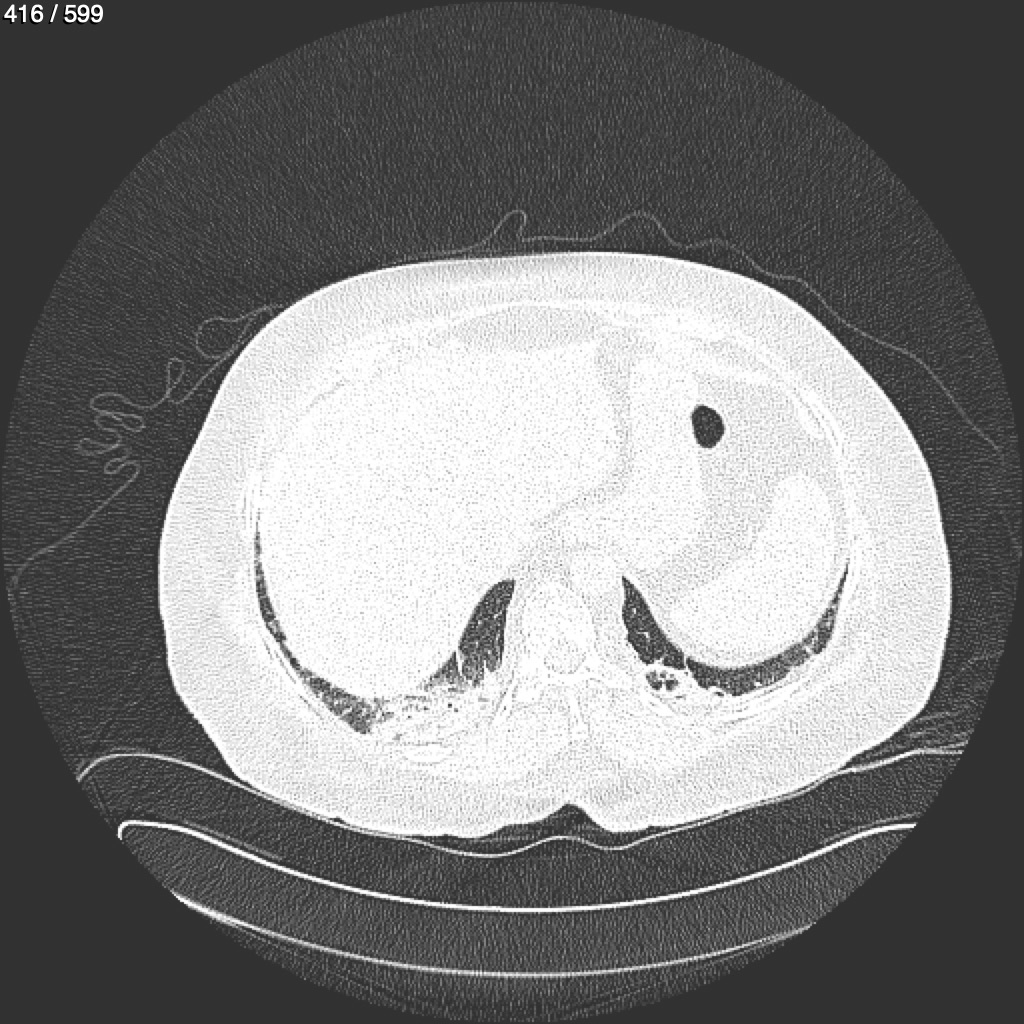

Home G​l​o​r​i​a​ ​G​l​a​d​y​s​ ​B​e​a​s​l​e​y​ ​-​ ​T​ó​r​a​x​ ​T​o​r​a​x​_​S​i​m​p​l​e​ ​(​A​d​u​l​t​o​)